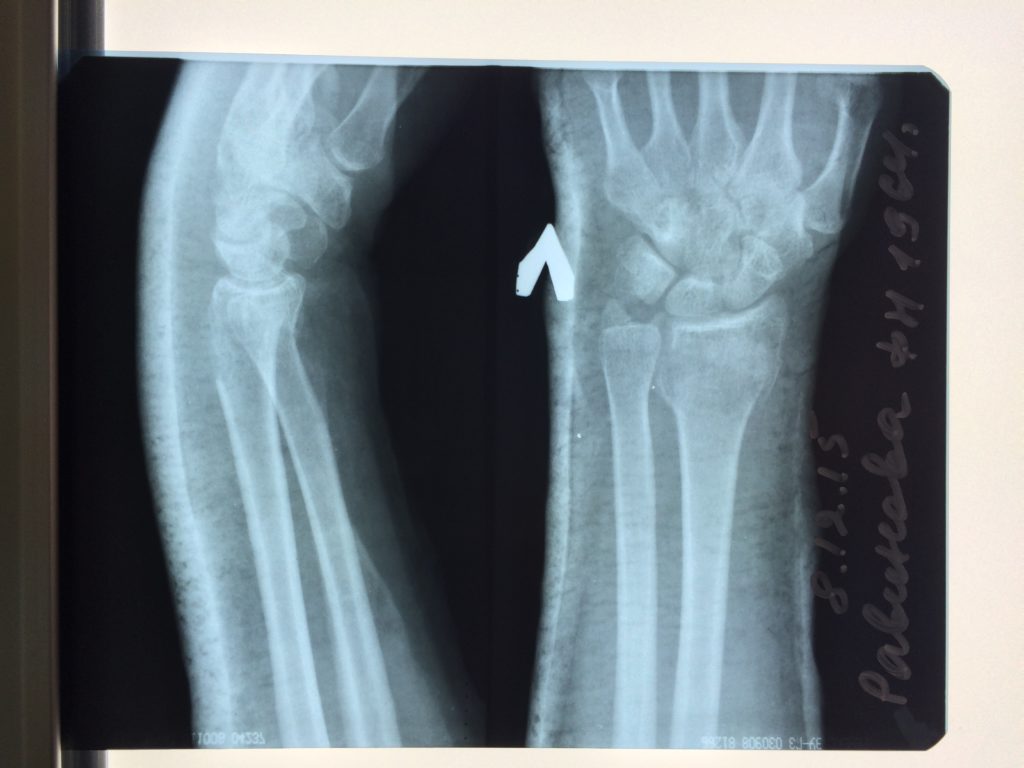

Операция - открытая репозиция, остеосинтез лучевой кости пластиной с костной ксенопластикой материалом "Остеоматрикс". На контрольных снимках в три месяца имеется консолидация перелома, миграции фиксатора нет, имеется остеоинтеграция ксенопластического материала.

Отдаленные результаты через 6 (шесть) месяцев